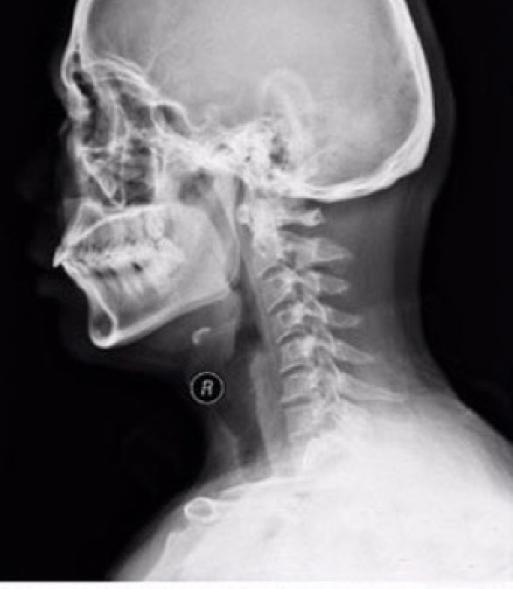

我们正常的颈椎是这样的:

你看出区别了吗?&*&*&*总之就是正常的颈椎应该是轻度向前弧度的,如果弧度变小或成为直线就称为生理弧度消失,如果变成向后方弧度,医生一般会报告“颈椎反弓”。